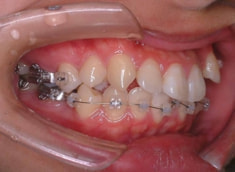

治療開始時

上下顎とも前突しており、叢生もあります。分析値からも抜歯対象症例です。

左右の非対称が骨格的にも、歯槽的にも存在し、特に顎の中での上下の歯の位置に、下顎前歯一本分の左右のズレが認められるので、かなり強い非対称といえます。